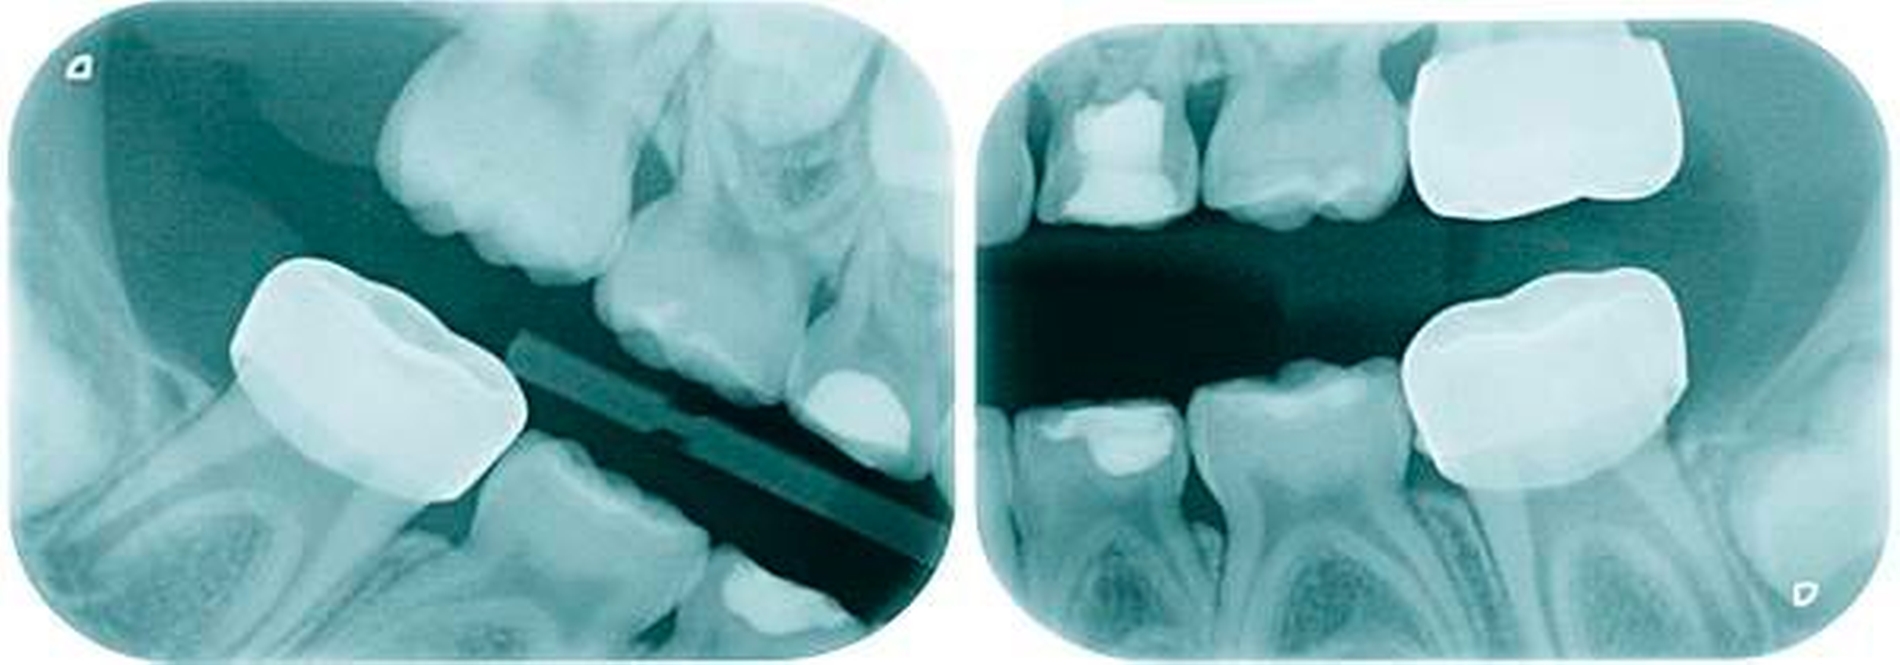

Aufgrund der noch nicht eindeutigen Gebissentwicklung des Patienten und der Tendenz zum Engstand wurde in Absprache mit den Eltern, dem Hauszahnarzt und dem Kieferorthopäden die Entscheidung getroffen, dass die stärker betroffenen und sehr empfindlichen Zähne 26, 36 und 46 mit Stahlkronen versorgt und Zahn 16 neu versiegelt werden sollte (Abbildungen 6 bis 8).

Stahlkronen der Sechsjahrmolaren sind ähnlich anzuwenden wie die etwas besser bekannten Stahlkronen im Milchgebiss. Im Gegensatz hierzu ist jedoch auf eine möglichst schonende Präparation zu achten, um genügend Substanz für die spätere definitive Versorgung zu erhalten, die bis zum 15. Lebensjahr erfolgen sollte.

Die konfektionierten Kronen kommen in den Fällen zur Anwendung, wenn die Zähne zumindest über einen gewissen Zeitraum erhalten werden sollen, die Defekte jedoch zu groß für die Füllungstherapie sind.

Leider ist die Präparation der Sechsjahrmolaren oft zeitraubender und geht meist mit erheblichem Substanzverlust einher. Nach versuchter schonender tangentialer Präparation mesial und distal sowie Reduktion der Höhe um circa 1,5 mm wird die entsprechende Kronengröße ausgewählt. Diese kann noch durch Kürzen oder Biegen des Randes individualisiert werden. Wichtig ist es, vor dem definitiven Einsetzen der Kronen den korrekten Sitz mittels Röntgenbild zu überprüfen. Bedingt durch das Fehlen eines basalen Schmelzwulstes lässt sich die Konfektionskrone trotz eines elastischen Federrandes auf dem konisch beschliffenen Zahn nur schwer fixieren. Störungen der Okklusion sind die Norm (noch unproblematisch im beginnenden Wechselgebiss), ein exakter Randschluss ist praktisch nicht zu erreichen. Insbesondere interdental, am Übergang zwischen Krone und Zahn, sind in jedem Fall Retentionsnischen vorhanden, die die Ansammlung von Plaque begünstigen. Folgeproblem ist Sekundärkaries und eine dauerhafte Irritation des marginalen Parodontiums. Verbleiben die Kronen über das 15. Lebensjahr hinaus im Mund, muss mit zum Teil erheblichem Knochenabbau gerechnet werden!